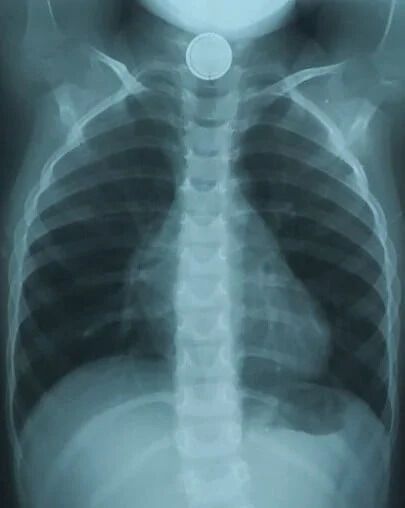

В Днепре трехлетний ребенок проглотил круглую батарейку. Из-за этого малышу понадобилась срочная операция.

Об этом сообщает телеканал D1. Батарейка пробыла в пищеводе малыша полтора часа и успела окислиться.

Медики провели специальные обследования и с помощью эндоскопического вмешательства удалили посторонний предмет.

На четвертый день после операции ребенку провели контрольную эзофагоскопию – осмотрели внутреннюю поверхность пищевода. На месте, где была батарейка, у маленького пациента обнаружили дефект слизистой – элемент электропитания повредил пищевод.

Батарейка пробыла в пищеводе малыша полтора часа dqxikeidqxitkant

Элемент электропитания повредил пищевод